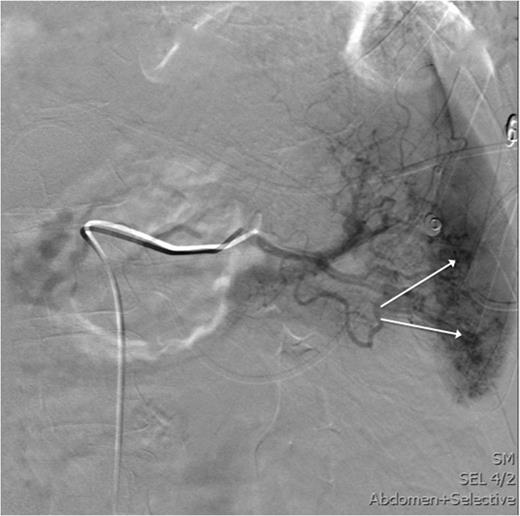

After the secondary survey, the patient was subjected to a computed tomography (CT) study, which showed a Grade IV splenic injury per the American Association for the Surgery of Trauma injury grading score with contrast extravasation (Fig. 1), a lower lobe contusion of the left lung, fractures of the IV and VI–XI ribs on the left side and bilateral iliac wing fractures. The pancreatic parenchyma was well perfused and homogenous in a portal venous phase CT-imaging (Fig. 2).

Axial view of the initial CT scan depicting a normally perfused pancreatic tissue.

After the CT study, angiographic embolization of the splenic artery was performed. Angiographic catheter was inserted through the right femoral artery and guided into the splenic artery through the celiac trunk. The Spongostan (Ethicon Inc., Somerville, NJ, USA) particles were deployed to the branches of the splenic artery as the contrast leakage was seen in multiple locations. The proximal SAE with three Gianturco coils (Cook Medical Inc., Bloomington, IN, USA) and one Azur Peripheral HydroCoil (Terumo Medical Corporation, Somerset, NJ, USA) were deployed 4 cm distal to the celiac trunk (Figs 3 and 4). After the procedure, the patient was admitted to intensive care unit.

This image shows an angiography of the splenic artery observing splenic contrast leak (white arrows).